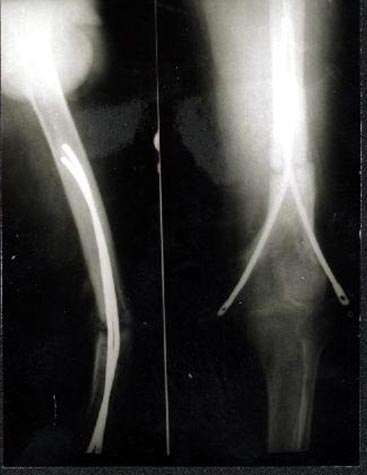

骨髓细胞与骨折愈合:骨髓中骨祖细胞可转化为成骨细胞,具有促进骨修复的作用,应用于临床也取得满意的效果。用髓内钉固定后保证早期稳定性,植骨补充成骨所需基质,骨髓骨祖细胞,可分化成为骨痂组织,骨生长因子促进骨折处再血管化,促进了骨不连的愈合。 病例介绍 病例一、患者63岁,股骨髁上骨折骨不连10年,曾先后4次手术,均采用钢板固定均松脱或折断而失败。 我们采用逆行髓内钉内固定,以及骨髓细胞复合生长因子植骨术,术后1年X线片连续性骨痂形成,膝关节功能良好。